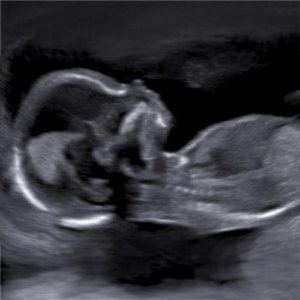

Fantastisch, je bent zwanger!

Zijn jullie ook zo nieuwsgierig naar het kindje in je buik? Laat dan een pretecho maken in 2D of 3D/ 4D met Realistic View.